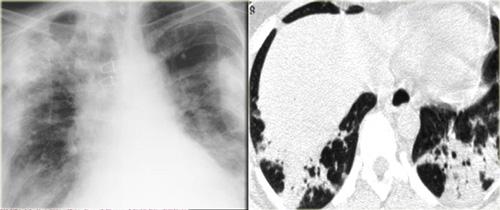

Đây là hình ảnh X-quang ngực điển hình của sarcoidosis giai đoạn muộn (giai đoạn IV) với xơ hóa ở vùng trên phổi và mất thể tích thùy trên dẫn đến nâng cao rốn phổi.

Xơ hóa gây tắc nghẽn các mạch máu phổi, có thể dẫn đến tăng áp động mạch phổi.

Đây là một trường hợp khác của sarcoidosis giai đoạn IV.

Lưu ý sự phân bố của các khối hợp lưu xơ hóa ở phần sau của phổi.

Ngoài ra còn có nhiều nốt nhỏ bờ rõ.

Một số nốt trong số này có phân bố dưới màng phổi điển hình.

Đây là một trường hợp sarcoidosis phế nang.

Hãy cuộn qua các hình ảnh.

Hình ảnh trông giống như tăng tỷ trọng dạng kính mờ, nhưng khi quan sát kỹ hơn có thể nhận thấy rằng sự tăng tỷ trọng này là kết quả của nhiều nốt nhỏ tập hợp lại.

Cũng lưu ý hạch to rốn phổi.

Sarcoidosis phế nang (2)

Bên trái là bệnh nhân nữ 47 tuổi với triệu chứng ho khan, khó thở nhẹ và xét nghiệm máu bình thường.

Bệnh nhân được chụp X-quang ngực và điều trị kháng sinh.

Phim kiểm tra được chụp lại do bệnh nhân không cải thiện.

Phim X-quang ngực đầu tiên cho thấy đông đặc hai bên ở thùy dưới (mũi tên), ban đầu được diễn giải là nhiễm trùng.

Sau hai tuần điều trị kháng sinh, không có cải thiện.

Chẩn đoán phân biệt lúc này bao gồm u ác tính (ung thư phế quản phế nang hoặc u lympho), viêm phổi tăng bạch cầu ái toan, viêm phổi tổ chức hóa, bệnh Wegener hoặc một thể không điển hình của sarcoidosis.

Tiếp tục với hình ảnh HRCT.

Hãy cuộn qua các hình ảnh bên trái.

Có nhiều vùng đông đặc.

Các dấu hiệu kèm theo bao gồm hạch to rốn phổi và trung thất.

Chẩn đoán phân biệt trên hình ảnh CT về cơ bản giống như trên X-quang ngực.

Kết quả mô bệnh học xác nhận sarcoidosis phế nang.

Chỉ có một gợi ý duy nhất cho chẩn đoán, đó là sự hiện diện của các nốt nhỏ có thể nhận thấy ở hình 3, nhưng rất khó quan sát.

Trường hợp này minh họa rõ ràng rằng sarcoidosis thực sự là “kẻ bắt chước vĩ đại”.

Do đó, sarcoidosis cần được đưa vào danh sách chẩn đoán phân biệt của chúng ta!